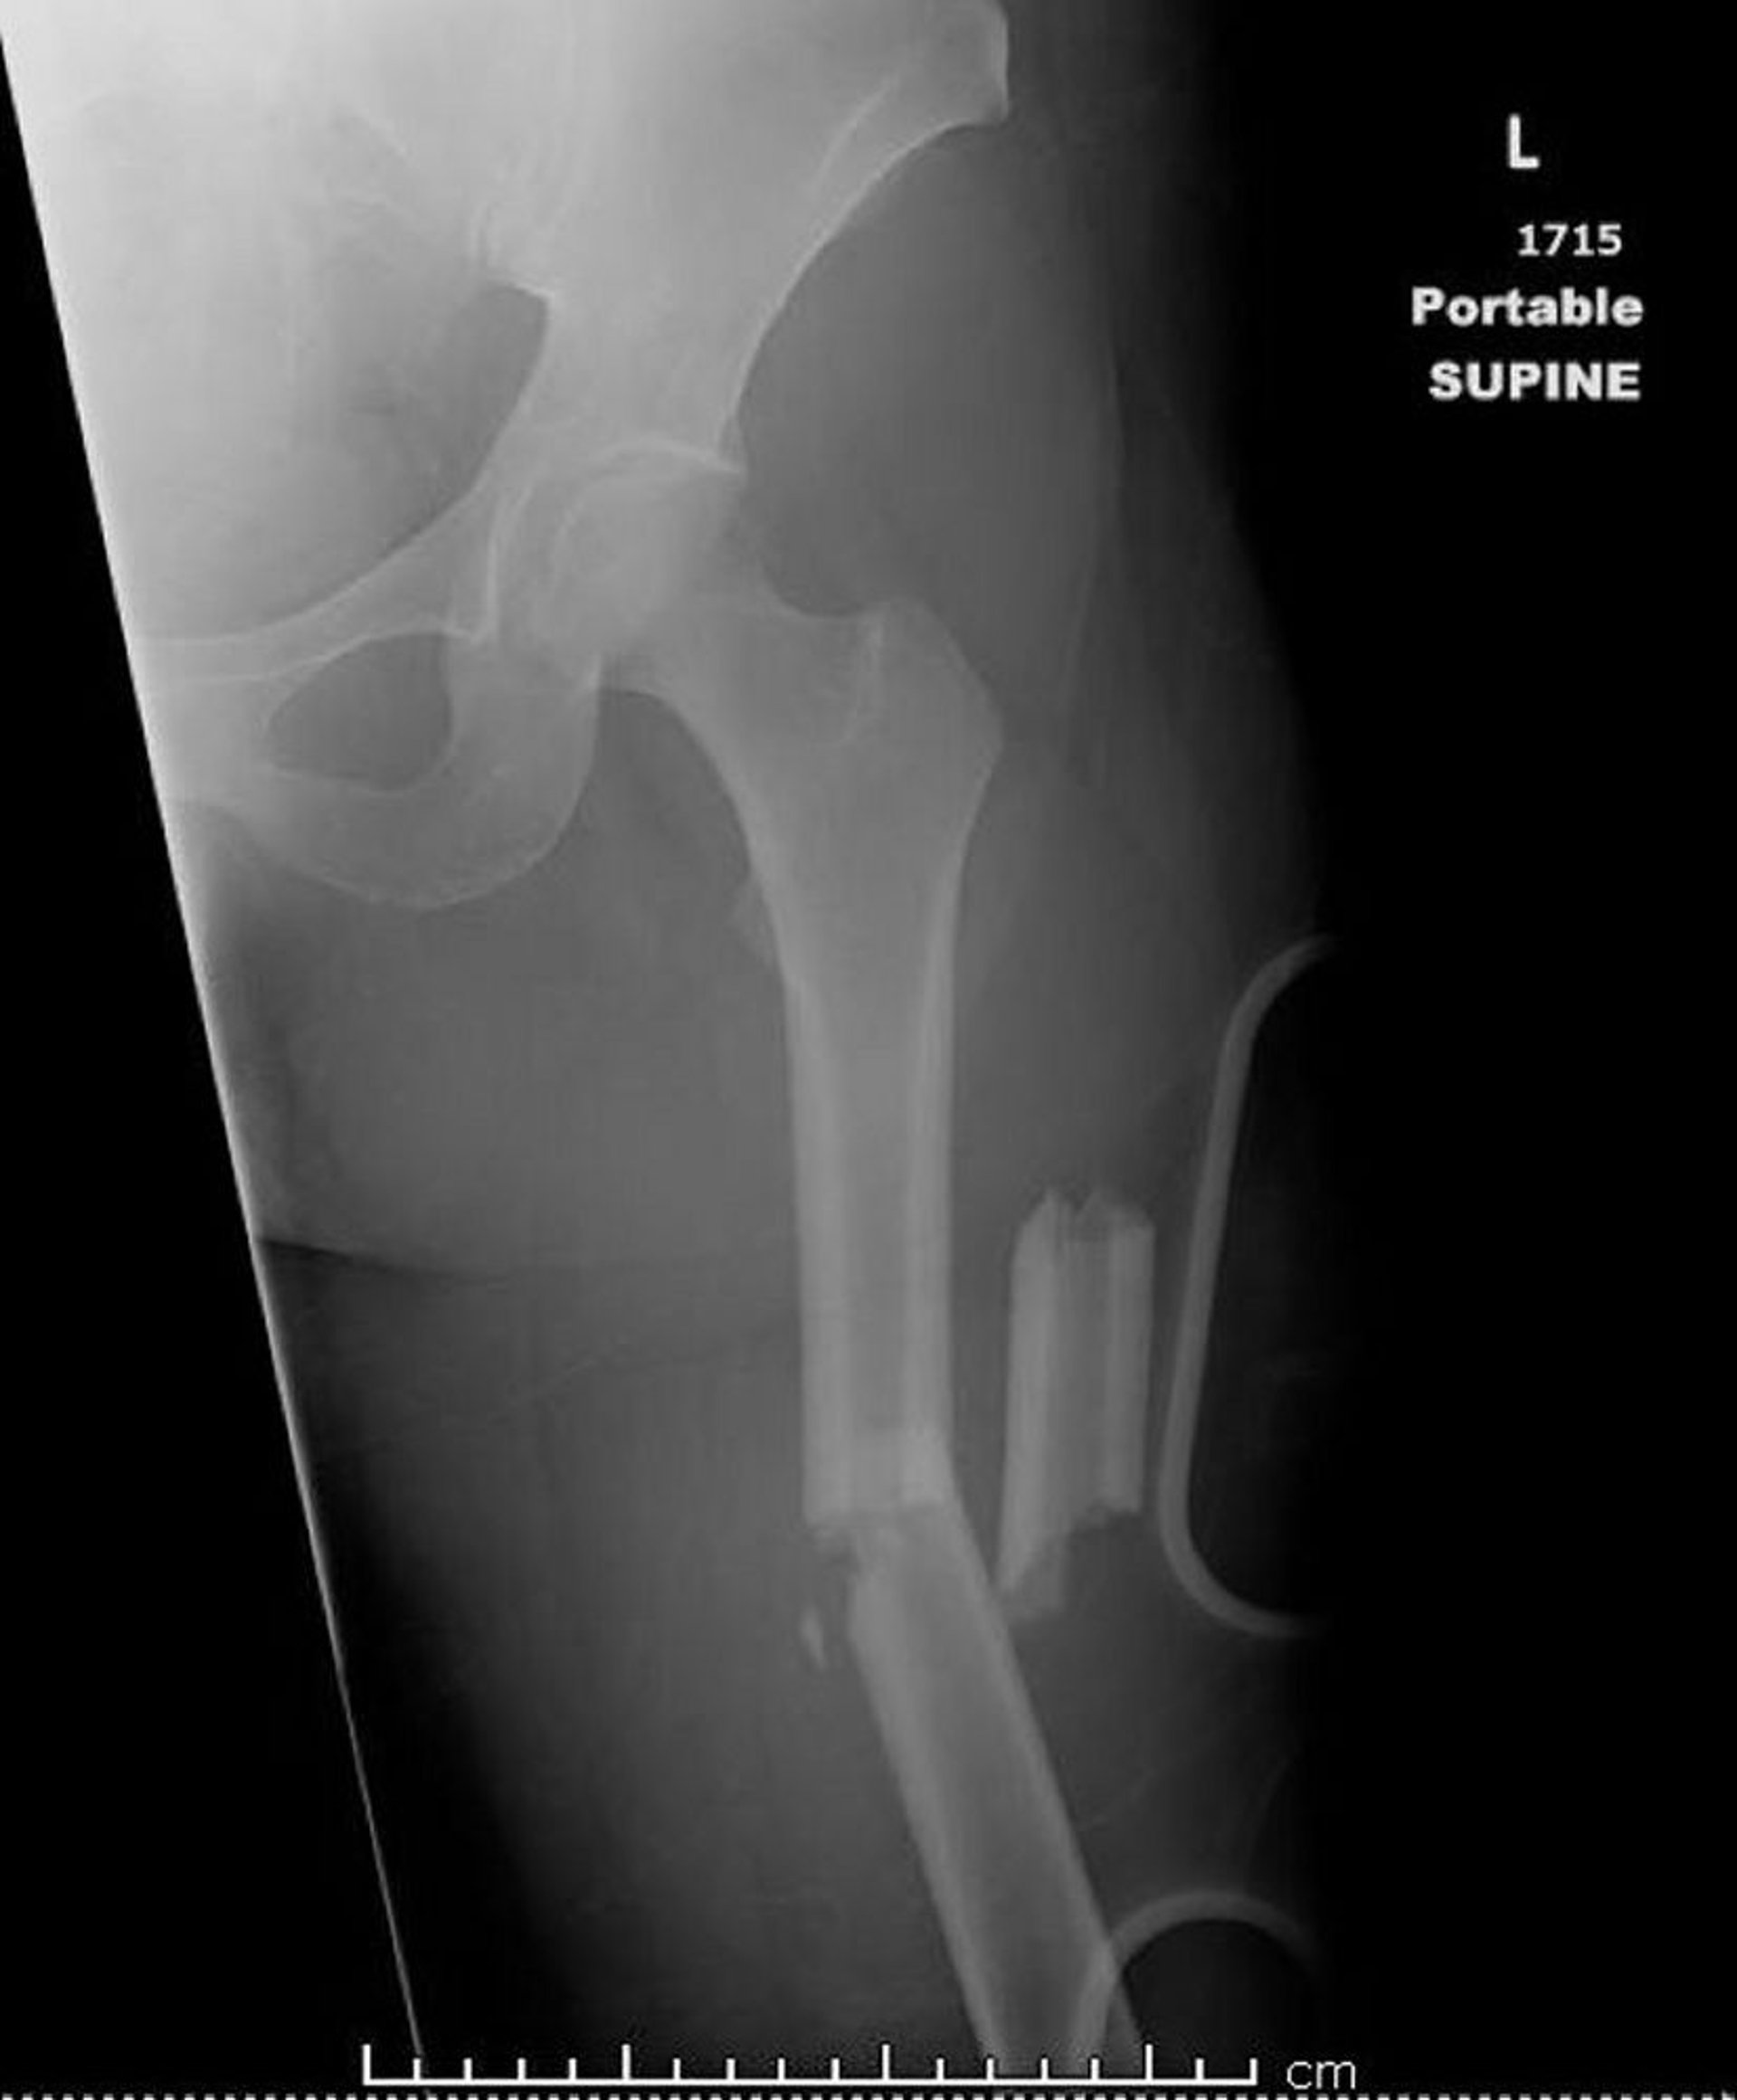

Fratura da diáfise média do fêmur (1)

Essa imagem mostra uma fratura cominutiva, angulada e encurtada da diáfise média do fêmur.

Imagem cedida por cortesia de Danielle Campagne, MD.